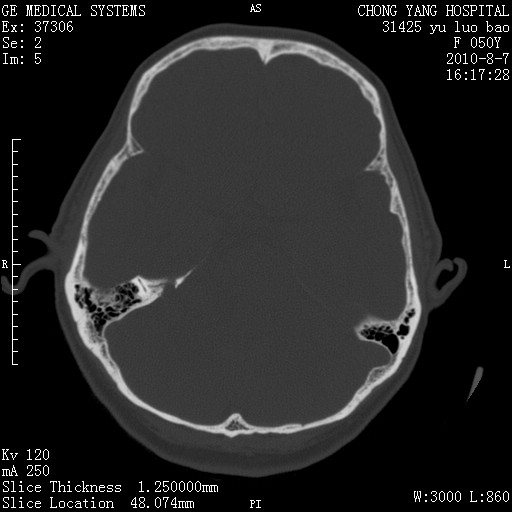

标题: CT28285:听力下降一年,头昏。

右侧桥小脑角去等密度占位,右侧内听道扩大、骨质吸收,考虑:右侧听神经瘤,建议增强检查。

右侧内听道扩大、骨质吸收,中脑受压左移,考虑:右侧听神经瘤,建议增强检查。支持!

骨窗示右侧内听道扩大,考虑右侧听神经瘤。

右侧桥小脑角区等密度占位,内耳道扩大,听神经瘤